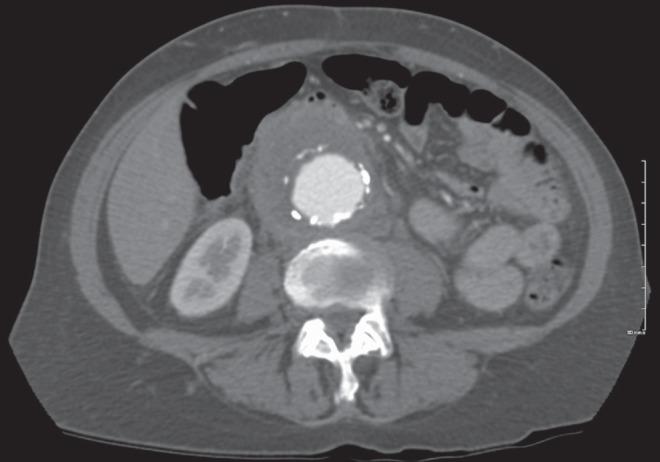

Khambati Husain, Brandys Tim

Division of Vascular and Endovascular Surgery, Ottawa Hospital and the University of Ottawa, Ottawa, Ontario.

Can J Infect Dis Med Microbiol. 2015 Sep-Oct;26(5):249-50. doi: 10.1155/2015/863275.